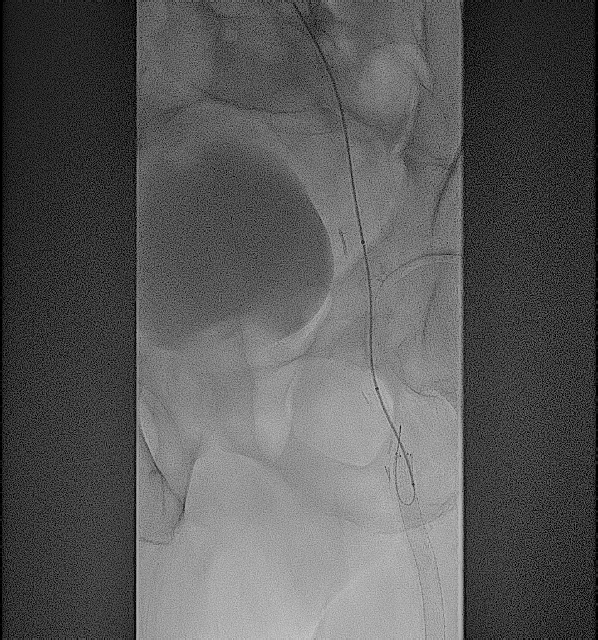

After gaining access into the SFA, the first step of crossing from the SFA into the femoral vein was done with the Endocross catheter (Endologix; Figure 5). Although it had to be done through stent struts, this proved to be fairly easily accomplished with minimal resistance. A 0.014-in Grand Slam wire (Asahi Intecc Medical) was snared from the Endocross to the femoral vein using a pre-existing snare. The crossover site was then dilated using a 5.0-mm Serranator balloon (Cagent Vascular; Figure 6), allowing for the Endocross to advance into the distal femoral vein for distal access into the P1 portion of the popliteal artery through a pre-existing Supera stent (Abbott Cardiovascular) with minimal resistance. This was pre-dilated with a 4.0-mm Coyote balloon (Boston Scientific) followed by a 5.0-mm Serranator balloon (Figure 7). After sufficient pre-dilatation, the Torus stents (Endologix) were placed from the distal anastomosis to proximal anastomosis (5.5 mm distally and 6.5 mm proximally; Figure 8) followed by post-dilatation with a 6.0-mm Mustang balloon (Boston Scientific; Figure 9). Repeat angiographic assessment showed good apposition and expansion of the stents and robust vessel runoff down to the foot (Figure 10). The patient’s wound did require transmetatarsal amputation but was spared an above-knee amputation. His wounds had shown sufficient healing 3 months from the principal procedure.